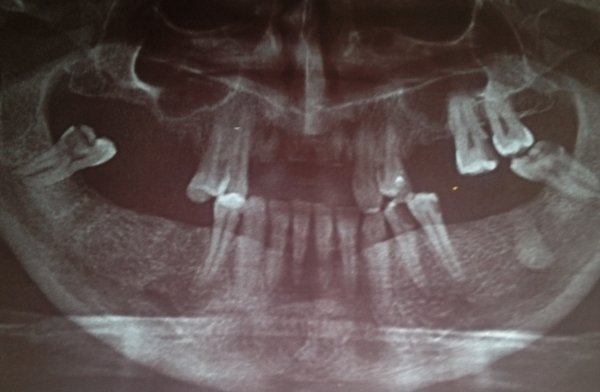

Здравствуйте! У меня вверху справа отсутствуют 4, 5, 6 зубы. А 2, 3 и 7-й депульпированы и подготовлены под протезирование. Какой протез можно поставить в данном случае? Сколько он будет стоить?

Добрый день. В вашем случае правильное решение - это, конечно, имплантация, альтернатива может быть только съемное протезирование. Вам необходимо посетить нашу клинику, так как протезов множество и они отличаются как по своей конструкции так и по цене.

Мостовидная конструкция в вашем случае противопоказана, слишком большой пролет.